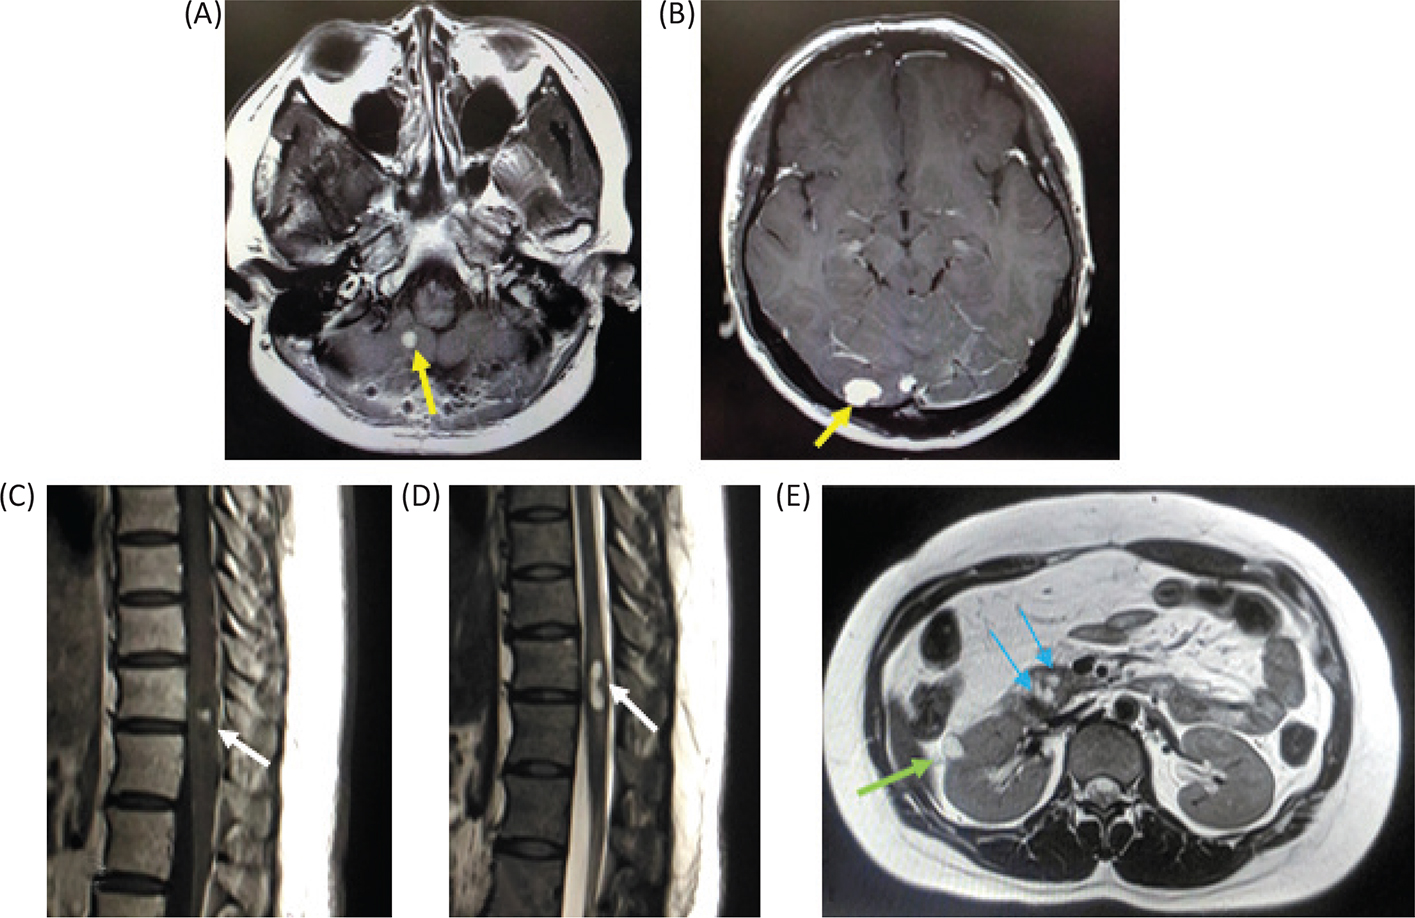

At the age of 26, the patient underwent surgical treatment for cerebellar hemangioblastoma. She also had a spinal cord hemangioblastoma at 11th thoracic vertebra level, a renal cyst and multiple pancreatic cysts (Figure 2).

Fig 2

Figure 2. Magnetic resonance imaging of the patient. (A and B) Gadolinium (Gd)-enhanced T1-weighted image of cerebellum when the patient was 26 years old. The patient had multiple cerebellar hemangioblastomas. (C) Gd-enhanced T1-weighted image of the lower thoracic cord. A small hemangioblatoma with a syrinx is shown. (D) T2-weighted image of the lower thoracic cord. (E) T1-weighted image of the abdomen. A renal cyst and multiple pancreatic cysts are shown.